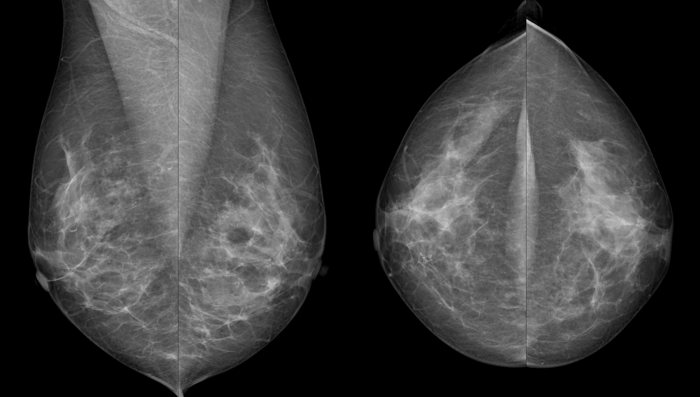

Von jeder Brust werden üblicherweise zwei Aufnahmen - jeweils von oben nach unten (cranio-caudale Aufnahme) und schräg von innen nach außen (medio-laterale oblique Aufnahme) - angefertigt. Die Brust wird dabei in eine Vorrichtung eingespannt und komprimiert:

Die cc-Aufnahme wird immer so dargestellt, dass die Außenseite der Brust im Bild oben liegt.

Die Kompression beeinflusst die Qualität der Aufnahme. Je dünner die Brust ausgestrichen ist, desto besser und klarer wird das Bild, wie das Beispiel unten zeigt.

Wir sehen dieselbe Brust im Abstand von zwei Jahren, die linke Aufnahme ist die neuere. Links erscheint die Brust wesentlich dichter, das Drüsen- und Bindegewebe ist unscharf, die Haut um die Brustwarze ist nur unzureichend abgebildet. Verdächtige Veränderungen könnten eventuell durch die schlechte Bildqualität überdeckt werden. Die Frau hatte an diesem Tag eine sehr druckempfindliche Brust, weshalb keine stärkere Kompression möglich war.